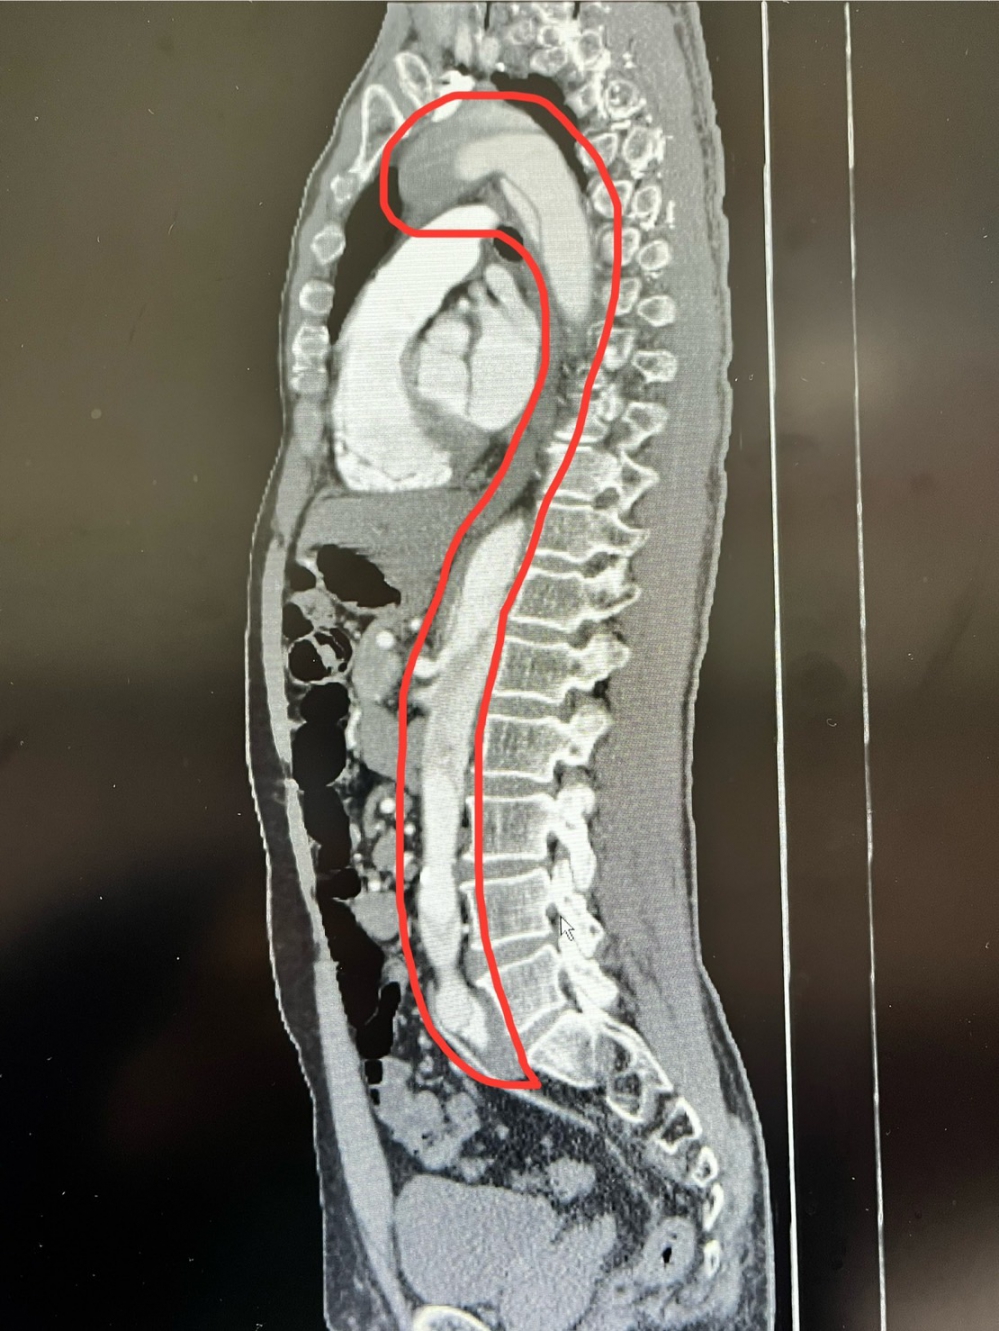

朱主任說,患者到院時主訴胸悶、頭暈、上腹痛,血壓只有91/56mmHg,胸痛形態不典型,很難診斷主動脈剝離,隨即安排心電圖、胸部X光、血液分析等檢查;接續安排電腦斷層,發現整條主動脈剝離。

圖:員榮醫療體系員榮醫院急診部主任朱偉岳,從電腦斷層掃描發現患者整條主動脈(圖中紅線圈處)都有嚴重剝離的情況,隨即安排患者接受手術